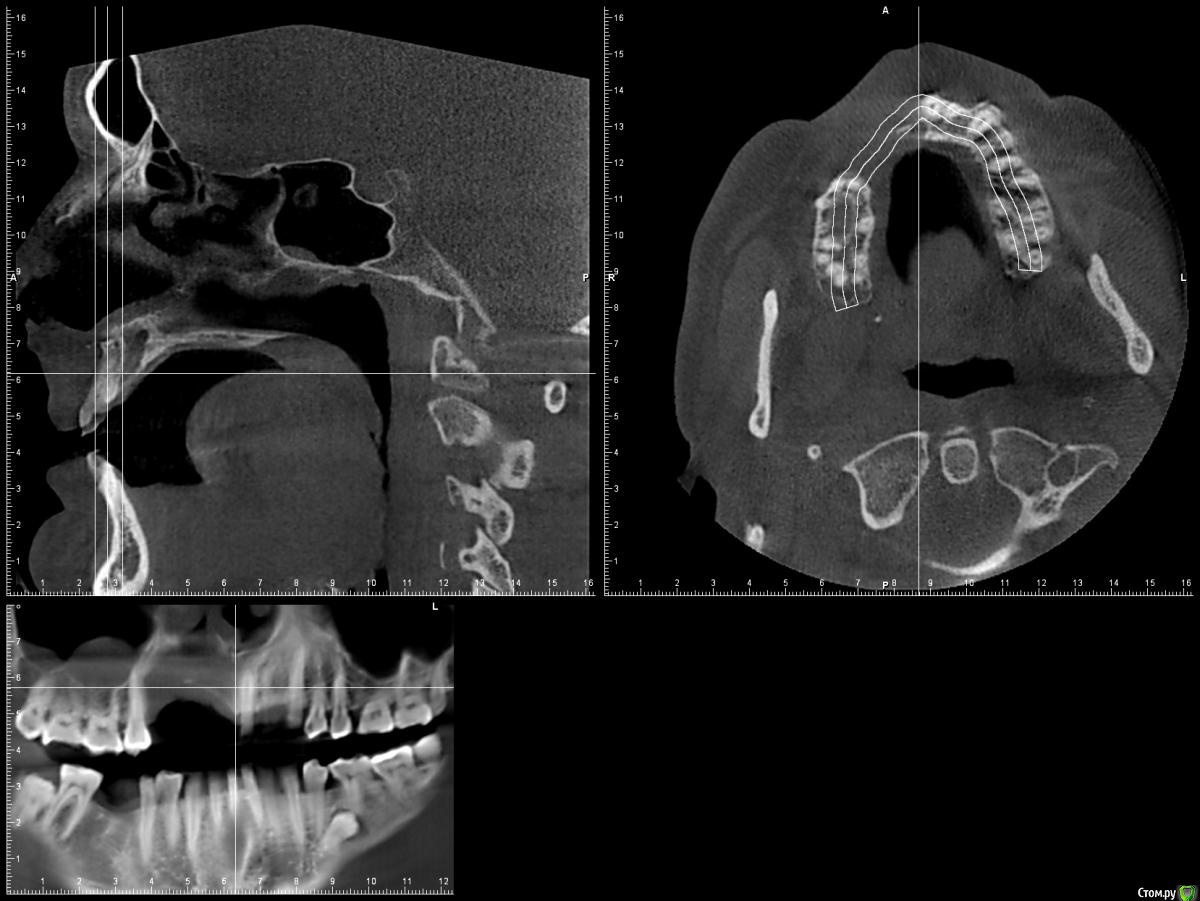

L.E.S.I.K. Опубликовано 13 июля, 2017 Поделиться Опубликовано 13 июля, 2017 Доброго времени суток, коллеги. Пациент обратился с желанием иметь несъемную конструкцию на имплантах. В анамнезе 5 мес назад операция по поводу хронического одонтогенного остеомиелита верхней челюсти. В настоящее время клинический признаков воспаления нет. Есть только значительный дефект. 3 класса по Зиберту. Какие возможны методы аугментации кости в объеме необходимом для имплантации? Мне на ум приходит только блоки из подвздошной Ссылка на комментарий

Bier Опубликовано 13 июля, 2017 Поделиться Опубликовано 13 июля, 2017 плохие очень снимки, толком ничего не понятно. Блоки с подвздошки забудьте, они резорбируются быстро. Тут нужен один из вариантов GBR Покажите нормальные срезы, чтобы был ясен уровень костных пиков на соседних зубах. Ссылка на комментарий

L.E.S.I.K. Опубликовано 13 июля, 2017 Автор Поделиться Опубликовано 13 июля, 2017 Возле 21 пик есть, а в обл 25 снижен, корень оголен на четверть. Смущает также отсутствие местами костно дна полости носа Ссылка на комментарий

Maxfac Опубликовано 13 июля, 2017 Поделиться Опубликовано 13 июля, 2017 Только реваскуляризированный лоскут. По анатомии дефекта подойдёт бедренный. Какова причина остеомиелита? Что с общей соматикой? Сколько лет? Ссылка на комментарий